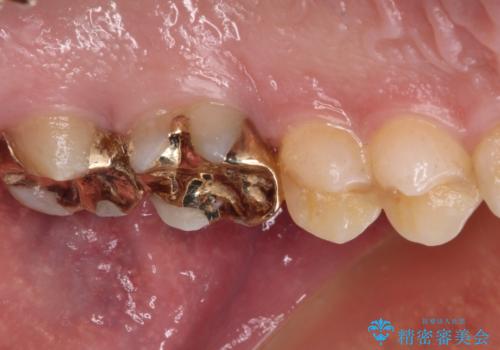

- 近医にて、銀歯の周りの歯が欠けてむし歯のようになっていると言われたとのことで来院された患者様です。

非常に咬合力が強く、銀歯やセラミックのような堅い素材では歯にダメージがかかり、治療を繰り返す可能性が高いと思われたので、ゴールドインレー(白金加金インレー、PGAインレー)にて、治療中の歯と銀歯が装着されている歯を修復治療することとしました。